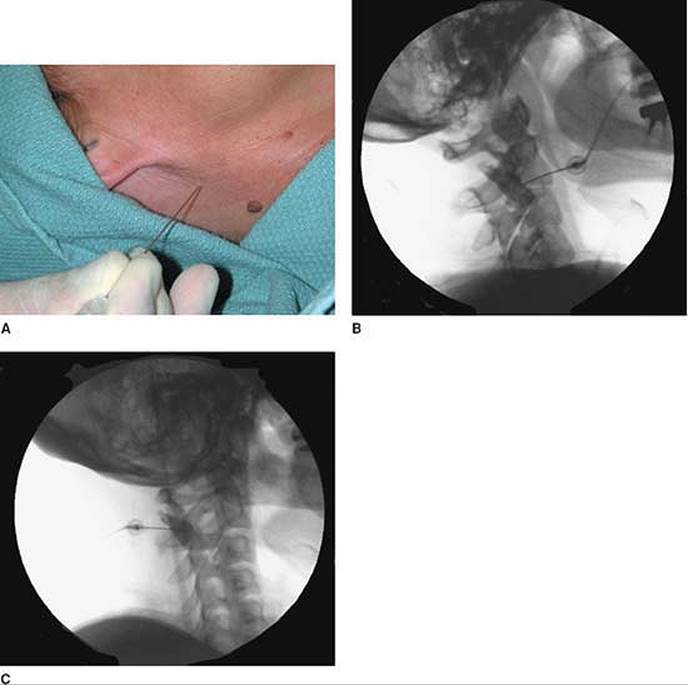

Approach and Technique: The cervical region is prepared and draped using sterile techniques. Under fluoroscopic guidance, the cephalocaudad vertebral level of the facet to be blocked is marked (Fig. 64-1A). The mediolateral position of the facet joint is also visualized by rotating the fluoroscope to produce an oblique image of the cervical spine. After negative aspiration of blood and cerebrospinal fluid (CSF), needle placement is confirmed with an injection of radiocontrast material. This is then followed with local anesthetic and steroid.

Figure 64-1. Under fluoroscopic guidance, the cephalocaudad vertebral level of the facet to be blocked is marked.

For medial branch blocks (C3-7), the patient is positioned supine with the side to be blocked uppermost. A 20° to 30° oblique view is obtained by rotating the fluoroscope to visualize the foramina (in order to avoid them) and before proceeding with the injection. Figure 64-1B presents the lateral view (with dye) and Figure 64-1C presents the oblique view (with dye).